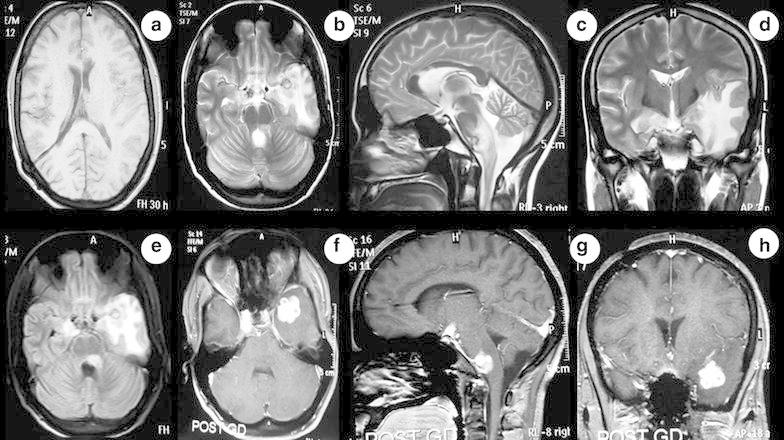

An 18-year old boy had mild grade fever, headache, recurrent vomiting and confusion for 2 months. The magnetic resonance imaging (MRI) of brain showed multiple intraparenchymal lesions involving brainstem and anterior temporal lobe. These lesions were isointense on T1-weighted (Fig. 1a), hyperintense on T2-weighted (Fig. 1b–d) and fluid attenuated inversion recovery (FLAIR) (Fig. 1e) images. There was no central hyperintensity on T2-weighted image. Perilesional vasogenic edema was present and Gadolinium-enhanced T1-weighted images (Fig. 1f–h) showed multiple ring enhancing conglomerate lesions. He was diagnosed as multiple intracranial tuberculomas with hydrocephalus. Ventriculoperitoneal shunt surgery was done and patient was started on first line antitubercular drugs (isoniazid, rifampin, pyrazinamide and ethambutol) along with corticosteroids and pyridoxine. At 2 month follow-up visit, he complained of acute onset weakness in both lower limbs and urinary incontinence for 5 days. There was no history of headache, fever, visual blurring, seizures, altered sensorium or noncompliance to treatment. On examination, higher mental functions, speech and cranial nerves including bilateral fundi were normal. The muscle power was medical research council (MRC) grade 2/5 in both lower limbs and normal in upper limbs. Deep tendon reflexes (knee and ankle) were exaggerated (+++) and Babinski sign were positive in both lower limbs. All the modalities of sensation including pain, touch, temperature, joint position and vibration were impaired below thoracic 5 (T5) spine level. There were no meningeal or cerebellar signs.

Fig. 1.

MRI of brain shows multiple intraparenchymal lesions involving brainstem and anterior temporal lobe. These lesions are isointense to grey matter on T1-weighted (a), hyperintense on T2-weighted (b, c, d) and fluid attenuated inversion recovery (FLAIR) (e) images. There is no central hyperintensity on T2-weighted image. Surrounding perilesional vasogenic edema is present. Gadolinium-enhanced T1-weighted images (f, g, h) shows multiple conglomerated ring enhancement. Ventriculoperitoneal shunt in situ is seen in right lateral ventricle